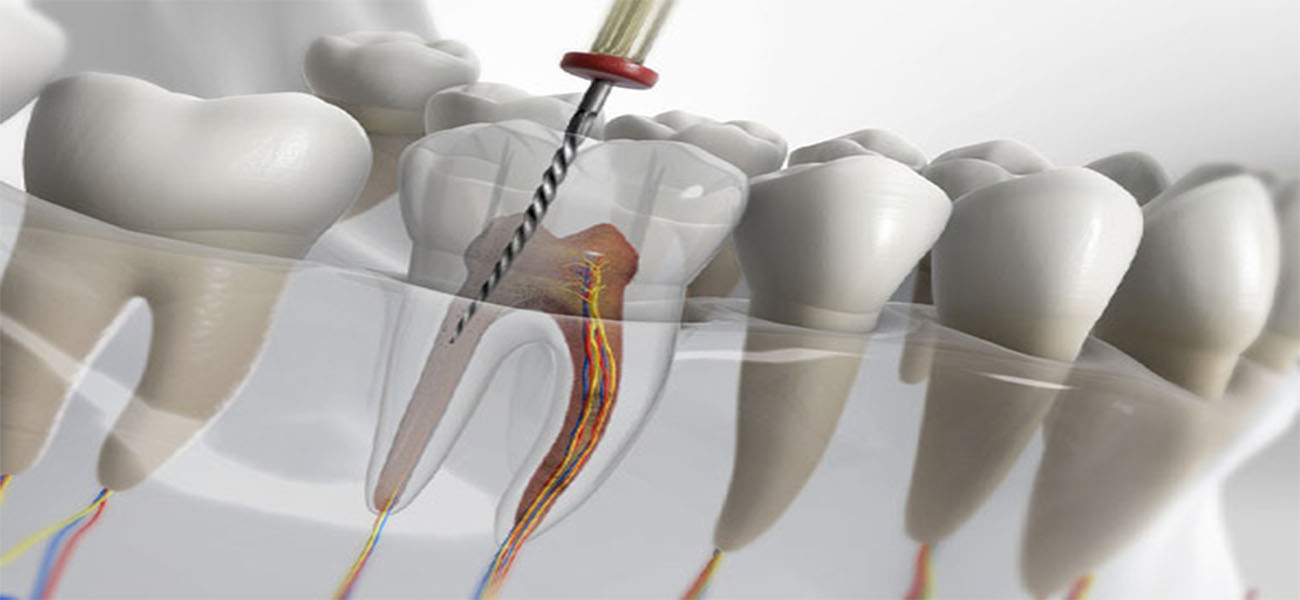

عصبکشی یا درمان ریشه، به منظور درمان عفونتها و آسیبهای دندانی انجام میشود. این فرآیند شامل حذف بافت عفونی از کانال ریشه دندان و پر کردن آن با مواد مخصوص است. عدم انجام این درمان میتواند منجر به درد شدید، عفونت و حتی از دست رفتن دندان شود.

عصبکشی یا درمان ریشه، یک فرآیند دندانپزشکی است که به منظور حذف بافت عفونی و آسیبدیده از کانال ریشه دندان انجام میشود. این درمان به حفظ دندانهای آسیبدیده و جلوگیری از عفونتهای بیشتر کمک میکند.